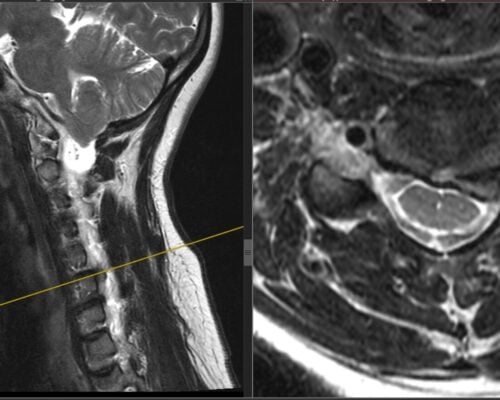

Studiu de caz: Spondiloză cervicală cu compresie medulară tratată prin decompresie ultra-laterală minim-invazivă – Recuperare neurologică rapidă

Spondiloza cervicală reprezintă una dintre cele mai frecvente cauze de afectare progresivă a măduvei spinării la pacienții peste 50 de ani. Problema majoră nu este lipsa tratamentului, ci întârzierea diagnosticului, deoarece simptomele inițiale sunt adesea subtile și atribuite procesului normal de îmbătrânire. Pacienții descriu frecvent dificultăți în activități fine, scăparea obiectelor din mână sau senzația […]

Studiu de caz: Spondiloză cervicală tratată prin abord anterior ultra-minim invaziv – decompresie și stabilizare cu recuperare rapidă

Spondiloza cervicală este o afecțiune degenerativă frecventă care poate determina compresia măduvei spinării și deteriorare neurologică progresivă. În multe situații, simptomele inițiale sunt subtile și pot fi ușor ignorate, mai ales la pacienții activi profesional, care își adaptează activitatea fără să conștientizeze evoluția bolii. Prezentăm cazul unei paciente în vârstă de 64 de ani, profesor […]